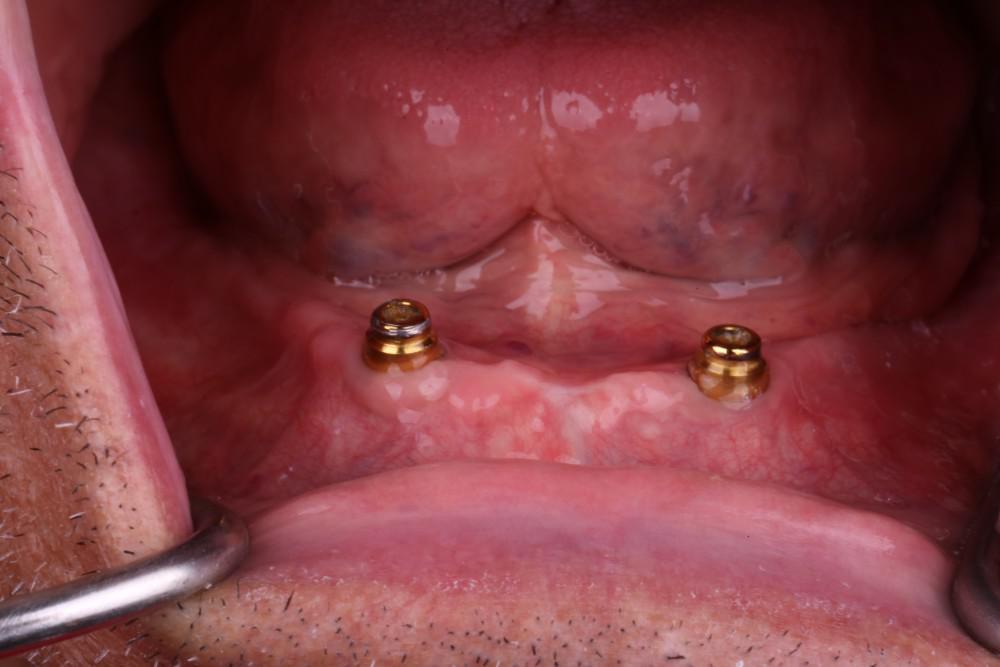

Mr. H does not have teeth and is using an old broken denture. He is looking for new oral rehabilitation cost-effectively. Four implants in the maxilla and two dental implants in the mandible were placed to retain the overdenture.